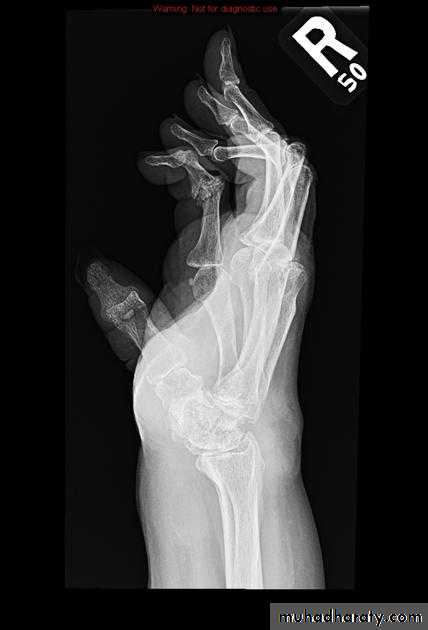

Severe erosive changes at radio-ulnar joints carpal bones at the metacarpal heads

Bilaterally symmetricSevere ulnar deviation

Severe erosions of MCPsComplete destruction of the wrist

Resorption of the carpals and the heads of the metacarpals

Radial deviation of the wrist

Rheumatoid wrist: articular destruction, carpal fusion and carpal collapse.

Severe destruction of the distal radius and ulna.Atlanto-axial subluxation in RA